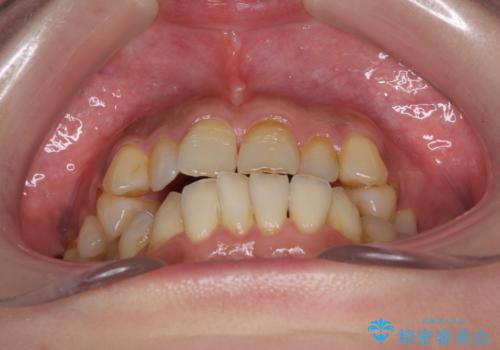

- 歯列不正と、どこで咬んで良いのか分からない咬み合わせを気にして来院された患者様です。

下顎骨は左側にシフトしており、咬み合ったときには奥歯と前歯の一部しか接触していない状態でした。

骨格的な左右差は歯列矯正は改善できないため、上下歯列が全体的に接触することをゴールとしてインビザラインにて矯正治療を行うこととしました。